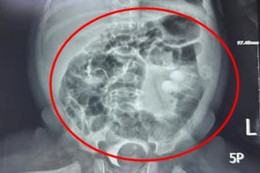

Phim chụp cộng hưởng từ (MRI) cho thấy có hình ảnh tổn thương não và tìm thấy thuốc diệt chuột trong bệnh phẩm xét nghiệm. Sau hơn 1 tuần điều trị tích cực, bệnh nhi xuất viện.